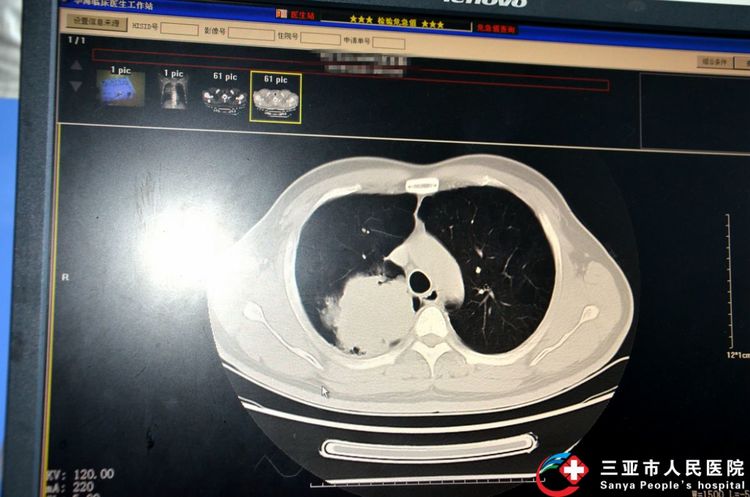

患者影像学和气管镜下图像资料

患者为49岁男性,因右肺肿物入住我院,曾经支气管镜常规活检未能明确肿物性质。呼吸内科团队经过术前讨论认为该患者有冷冻活检的适应症,在征得患者及家属同意后,制定了周密的手术方案和应急预案,在林容主任医师亲自指导下,由赵光强、王彬、陈运庭等医师合作顺利完成了经支气管冷冻活检,取得最大直径约10毫米的组织,比常规经支气管镜活检获取的标本大5-10倍,更有利于病理科医生做出诊断,指导临床治疗。经病理科检测对比,常规经支气管镜钳夹活检取得的组织样本大小为0.1-0.2cm,呈病理阴性;经支气管镜冷冻活检取出样本取得的组织样本大小为0.3-1cm,诊断为低分化癌,倾向于鳞癌。目前,患者精神状态良好,判明病因后就地在我院呼吸内科积极接受治疗。